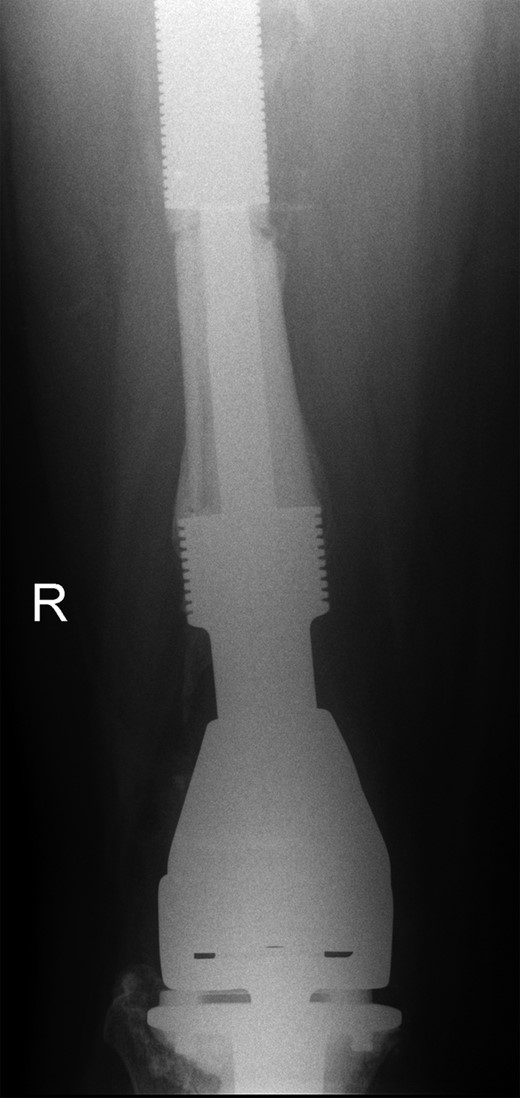

The operation was carried out by the senior author and the customized distal femoral prosthesis was successfully cemented over the pre-existing internal proximal femoral replacement (Figs 6 and 7).

Retained proximal femoral component with new custom-made cement-linked distal femoral prosthesis visible in lower half of the image.

New custom-made distal femoral prosthesis cement-linked to original salvage proximal femoral component visible in upper half of the image.